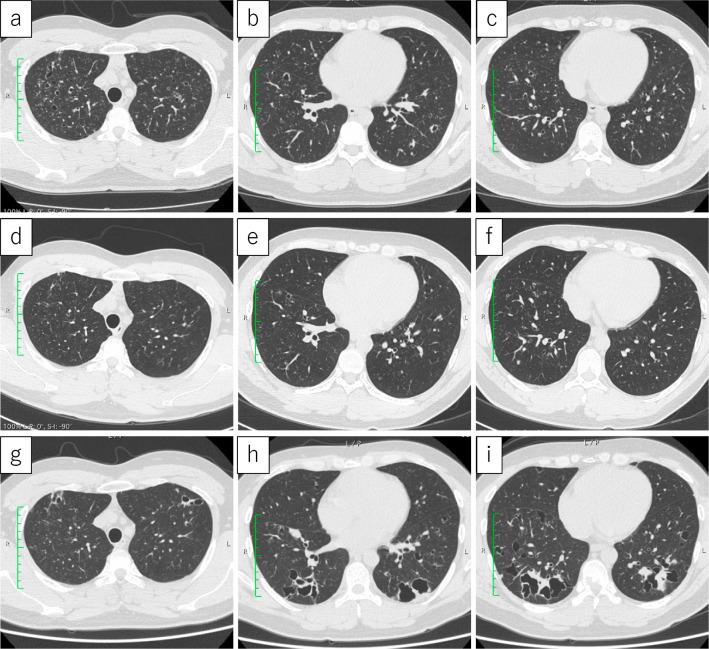

A 36-year-old Japanese man presented with cavities and nodular shadows in the lower lobes of his lungs and osteolytic lesions in the thoracic spine. He was diagnosed with multisystem Langerhans cell histiocytosis (LCH). Three years earlier, he had been noted to have small cavities and granular lesions noted in the upper lobes of his lungs, which later improved with smoking cessation. It was likely that his single-system pulmonary LCH (PLCH) progressed to multisystem LCH despite smoking cessation. Relapse or progression may occur in cases where PLCH lesions improve after smoking cessation. Thus, close follow-up is vital.

一位 36 岁的日本男性因肺部下叶的空洞和结节状阴影以及胸腰椎的溶骨性病变就诊。他被诊断为多系统朗格汉斯细胞组织细胞增生症(LCH)。三年前,他曾被发现肺部上叶有小空洞和颗粒状病变,后来戒烟后有所改善。尽管他已经戒烟,但他的单系统肺朗格汉斯细胞组织细胞增生症(PLCH)仍有可能进展为多系统 LCH。在戒烟后 PLCH 病变改善的情况下,可能会出现复发或进展。因此,密切随访至关重要。